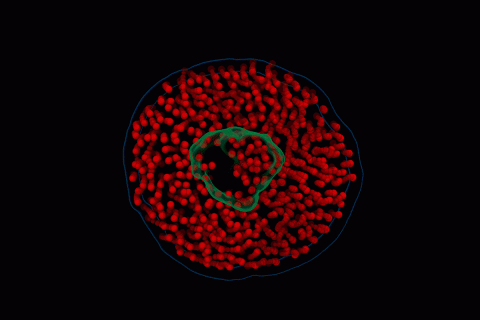

New Electron Videography Technique Captures Dance Between Proteins and Lipids

The new technique can be used to study the dynamics of other biomolecules, breaking free of constraints that have limited microscopy to still images of fixed molecules.